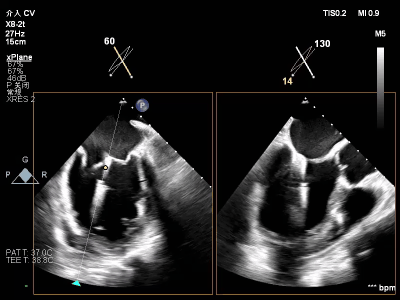

【术前超声心动图提示】

室性功能性二尖瓣反流(混合性MR),重度(MR 5+),反流位于2区–3区,左室射血分数低(EF27%)

【瓣膜与功能特点】

前超声评估明确关键指标:二尖瓣瓣环呈扩张状态(前后径约3.3cm,瓣环面积约4.75cm²,前叶长约2.1 cm,后叶长约1.4 cm),瓣叶增厚且后叶栓系明显,前后叶对合不良;同时伴左房、左室明显扩大,左室收缩功能显著减低,合并节段性运动异常。经团队综合评估,该患者为“多支冠脉支架植入后+低射血分数+重度功能性二尖瓣反流(混合性MR)”的高危病例,左室射血分数(EF)仅20%,在接受GDMT药物优化治疗6周后EF值提升至27%,但症状仍无法有效缓解,遂决定为其实施经心尖入路二尖瓣缘对缘修复术(TA-TEER)。

【术中操作(含关键步骤超声)】

鉴于患者术前心功能差、多支架植入的特殊情况,手术全程需兼顾“精准操作”与“保护心功能”双重要求:在全麻与经食道超声的协同引导下,团队先突破心功能受损导致的术野稳定性难题,稳步经心尖建立手术轨道与输送鞘;随后聚焦二尖瓣2偏3区精准置入一枚Ⅱf型夹合器,成功攻占这一解剖位置深、毗邻结构敏感、容错率极低而操作难度陡增的区域。